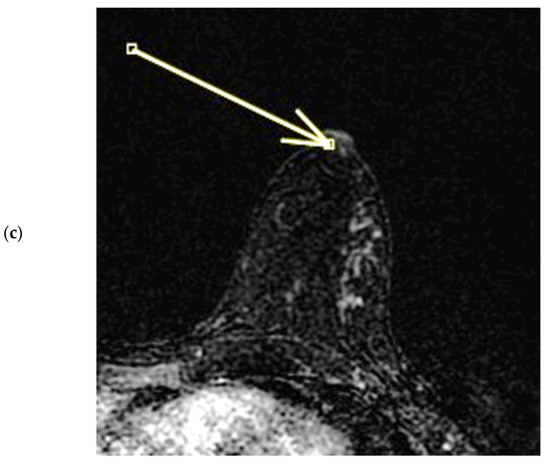

Figure 3.

(a,b) INE: internal nipple enhancement pattern (enhancement of the nipple below the NEZ but above the base of the nipple) during ce-MR. INE can have a patchy (a, arrow) or linear (b, arrow) morphology.